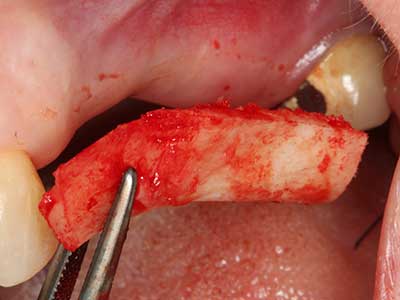

Abb. 3: Die basale Abtrennung des Blocks wird durch speziell abgewinkelte Aufsätze erleichtert.

Bei der Knochenblockentnahme zeigen sich weitere Vorteile für die Piezochirurgie: Neben der bereits beschriebenen hohen Präzision bei der Osteotomie stellt sich gerade die Verwendung der dünnen Sägespitzen als besonders materialschonend heraus. Bei der Verwendung insbesondere von Lindemannfräsen sind mit deutlich höheren Entnahmeverlusten durch die dickere Instrumentenspitze zu rechnen (Lakshmiganthan, Gokulanathan et al. 2012). Die insbesondere bei retromolar entnommenen Blocktransplantaten notwendige basale Abtrennung wird durch speziell hierfür vorgesehene rechtwinklige Sägen erleichtert, so dass die Piezochirurgie als präzises, übersichtliches und sicheres Verfahren zur retromolaren Knochenblockgewinnung angesehen wird (Happe 2007) (Abb. 1-12).